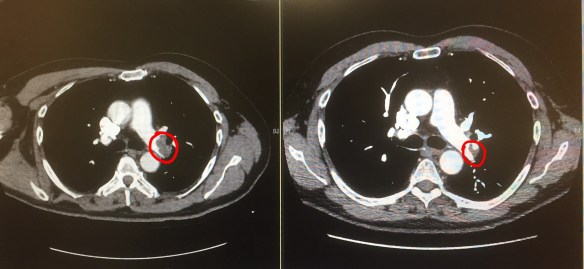

The dark artery-blocking embolus (circled in red) shrank between early February (L) and late March (R).